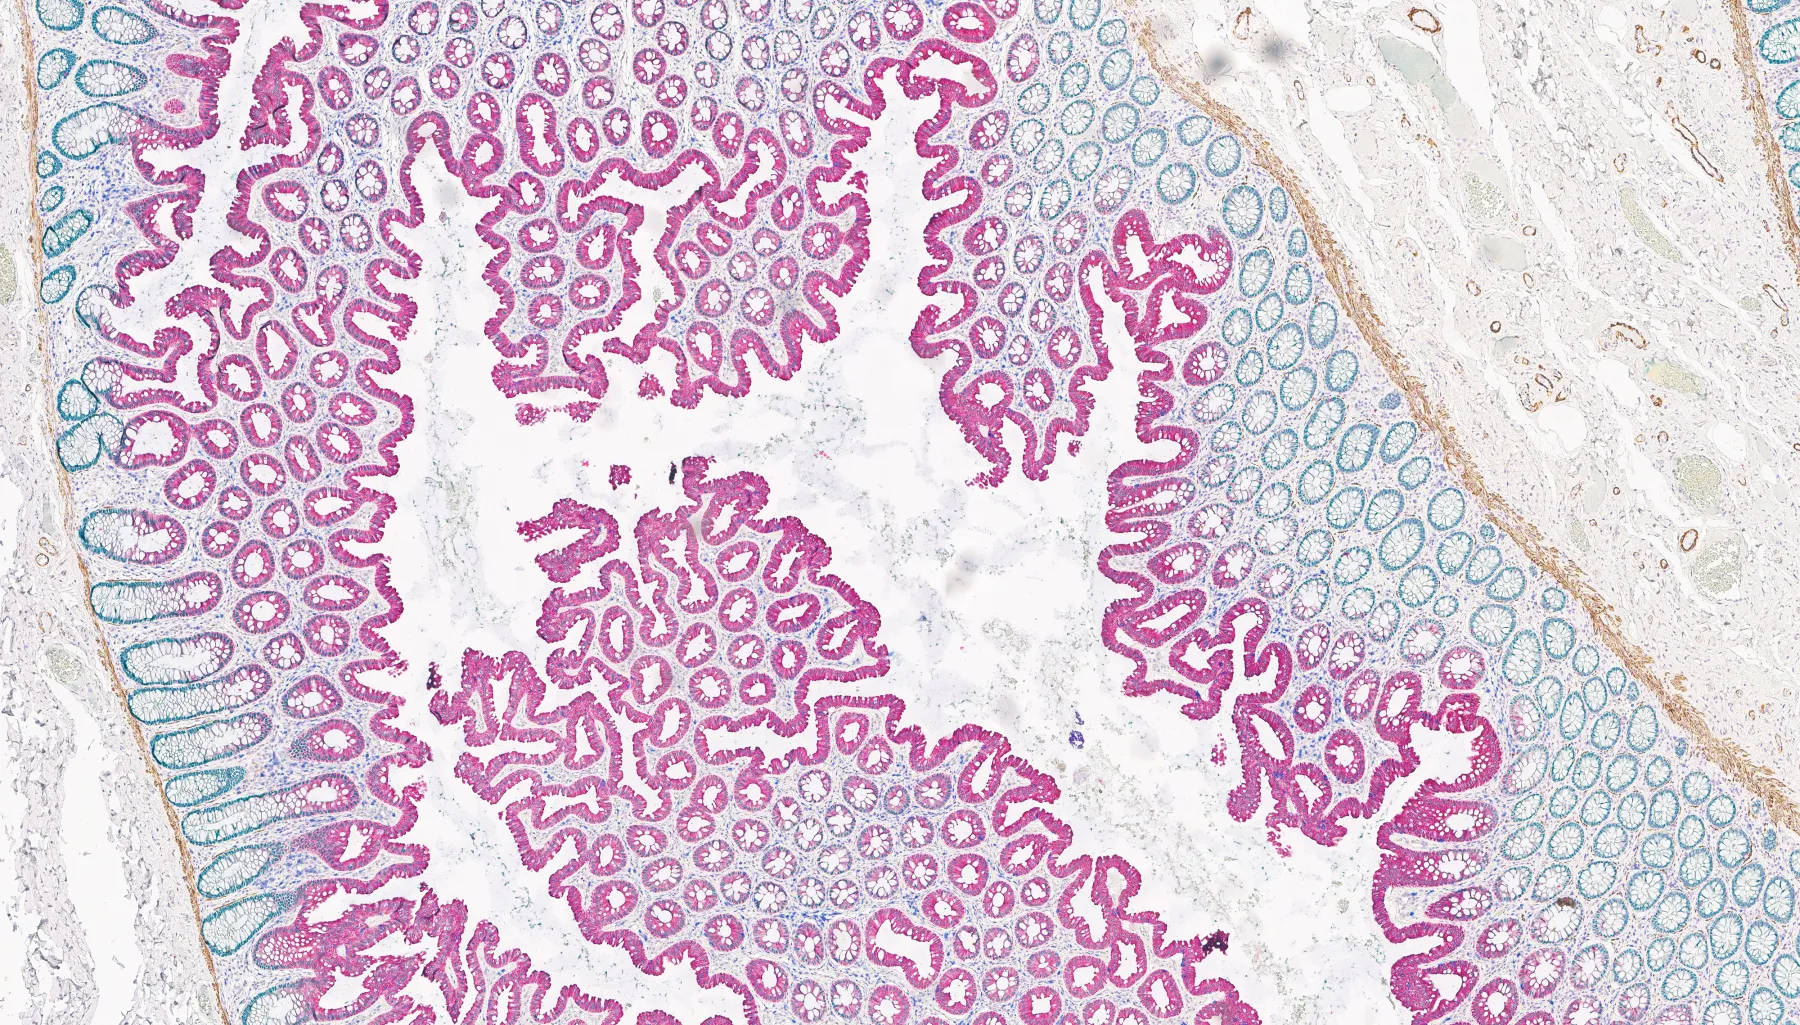

Colon tissue stained using the BOND RX and imaged with an Aperio digital pathology scanner.